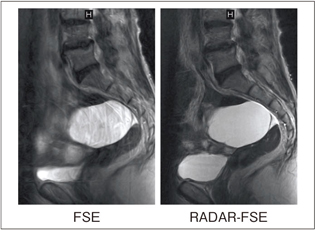

RADARによるモーションアーチファクト低減画像例を図8〜11に示します。

図8はSE法による頭部T1強調画像で,血流のアーチファクトがRADAR-SEの適用により低減されています。図9はパーキンソン病症例で,頭部のモーションアーチファクトが低減されています。図10は卵巣嚢腫症例で,腹壁の呼吸によるアーチファクトの顕著な低減効果が得られています。同様に,図11は子宮筋腫症例で,アーチファクトが低減されています。

![]() 図9 パーキンソン病T2強調画像 |